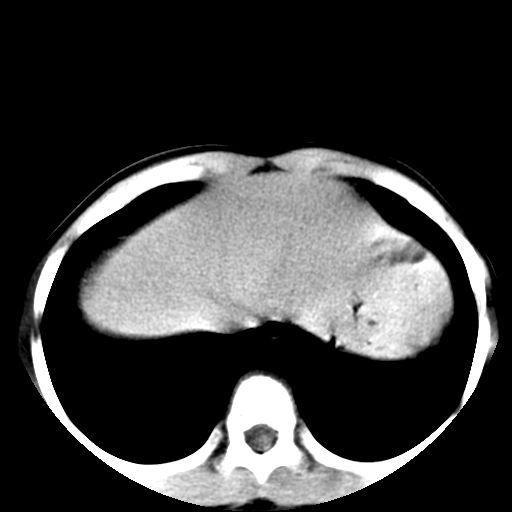

胸部明显是成年女性,定位象上双侧补过牙齿。轴位像上双侧乳腺退化。可以认定胸部与腹部不是一个人。

可以认定胸部与腹部不是一个人。

腹部好象未见异常。

腹部ct平扫未见明确异常

腹部ct平扫不能提示哪里有病变。